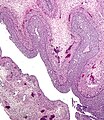

Luteinized follicular cyst

Luteinized follicular cyst is a benign finding in gynecologic pathology.

Features:[1]

- Stratified cuboidal/columnar epithelium-like cells with:

- Small nuclei and small nucleoli.

- Cytoplasm may be eosinophilic.

- Sit on spindled cells (theca interna) that is luteinized.